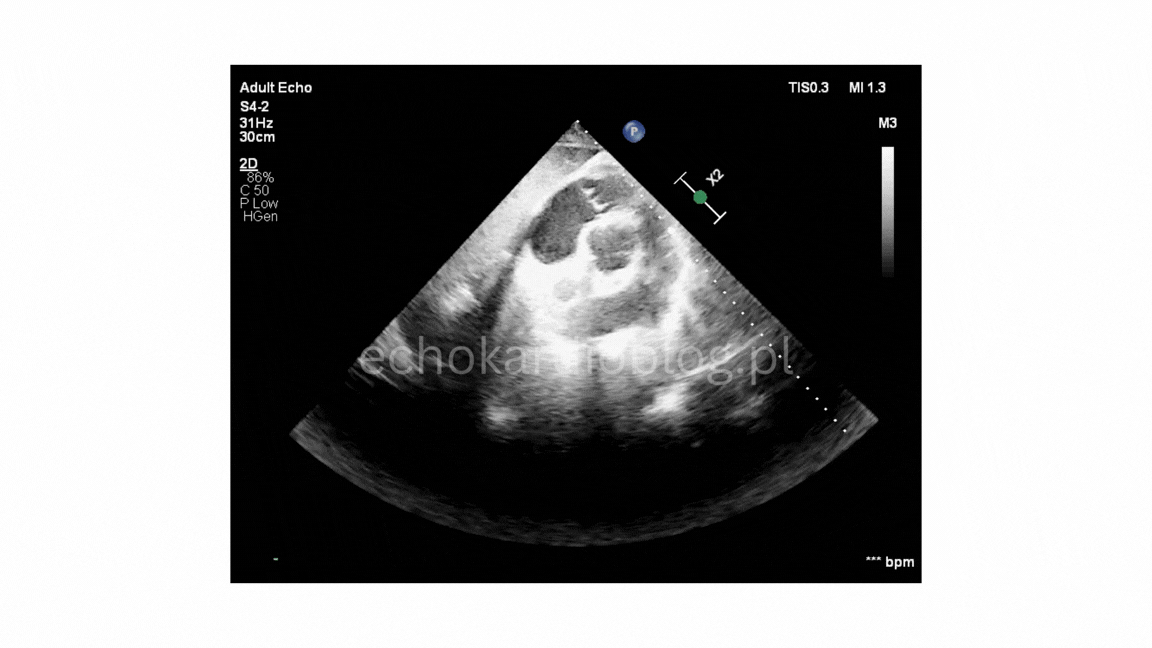

Pacjent , lat 66, przyjęty z podejrzeniem sepsy, w badaniu echokardiograficznym ujawniono duże, ruchome wegetacje na trzech zastawkach – mitralnej, trójdzielnej i płucnej . Wegetacje najlepiej widoczne były w projekcjach podmostkowych . Obraz jest dramatyczny: wysokie ryzyko powikłań zatorowych i przeciążenia prawego serca.

A 66-year-old patient admitted with suspected sepsis underwent echocardiography, revealing large, mobile vegetations on the mitral ,tricuspid and pulmonary valves .Vegetations were most clearly visualized in subcostal projections. The findings are dramatic, indicating a high risk of embolic complications and right heart overload.

ciężka niedomykalność płucna w projekcji podmostkowej

dwie długie i bardzo ruchome wegetacje na płatkach zastawki płucnej – pr podmostkowa w osi krótkiej